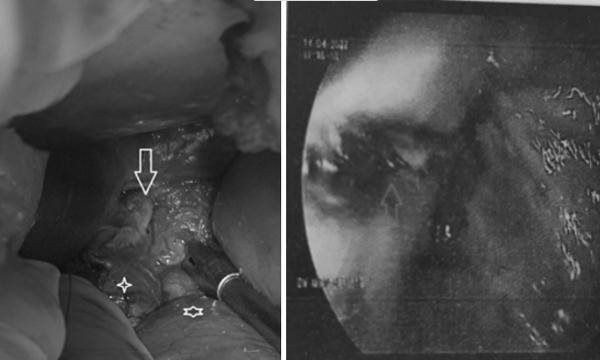

Hình ảnh thực quản trong nội soi dạ dày (bên phải) và lỗ thủng thực quản phát hiện khi phẫu thuật vùng bụng.

Kết quả thám sát vùng bụng thấy bụng bệnh nhân sạch nhưng quanh thực quản bụng và tâm vị bị bầm. Bơm chất chỉ thị màu, bác sĩ ghi nhận nam bệnh nhân có đường rách thực quản dài 3cm.